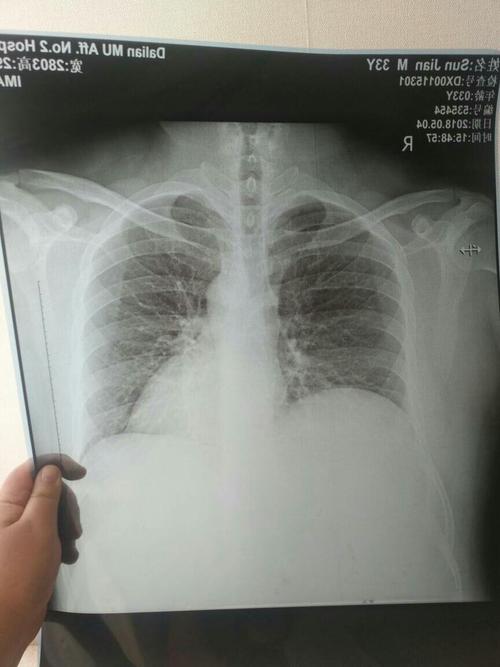

肺部图片胸片,胸片图片肺大泡

胸片

肺部胸片

胸片图片

肺部图片

肺部图片真实照片